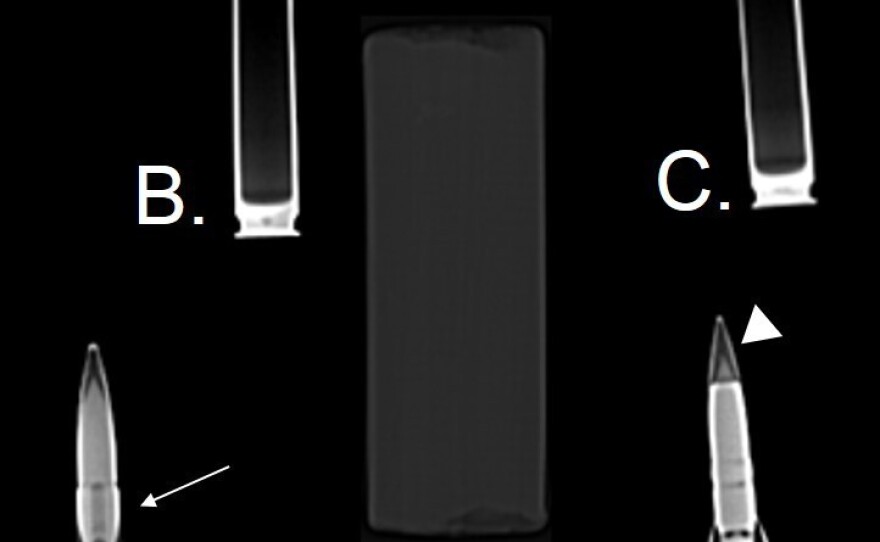

"It was awfully large and it wasn't a fragmented bullet, which is what we usually see," he says. "You could see the projectile, which was shaped like a bullet, but you could also see kind of a rim around it," says Newberry.

An explosives expert gave the team samples of bullets that were common in Afghanistan. The surgical team compared radiological images of them with ones they had of the object in the woman's skull.

They concluded that it looked like nonexplosive, but they couldn't be sure. They prepared for the worst.